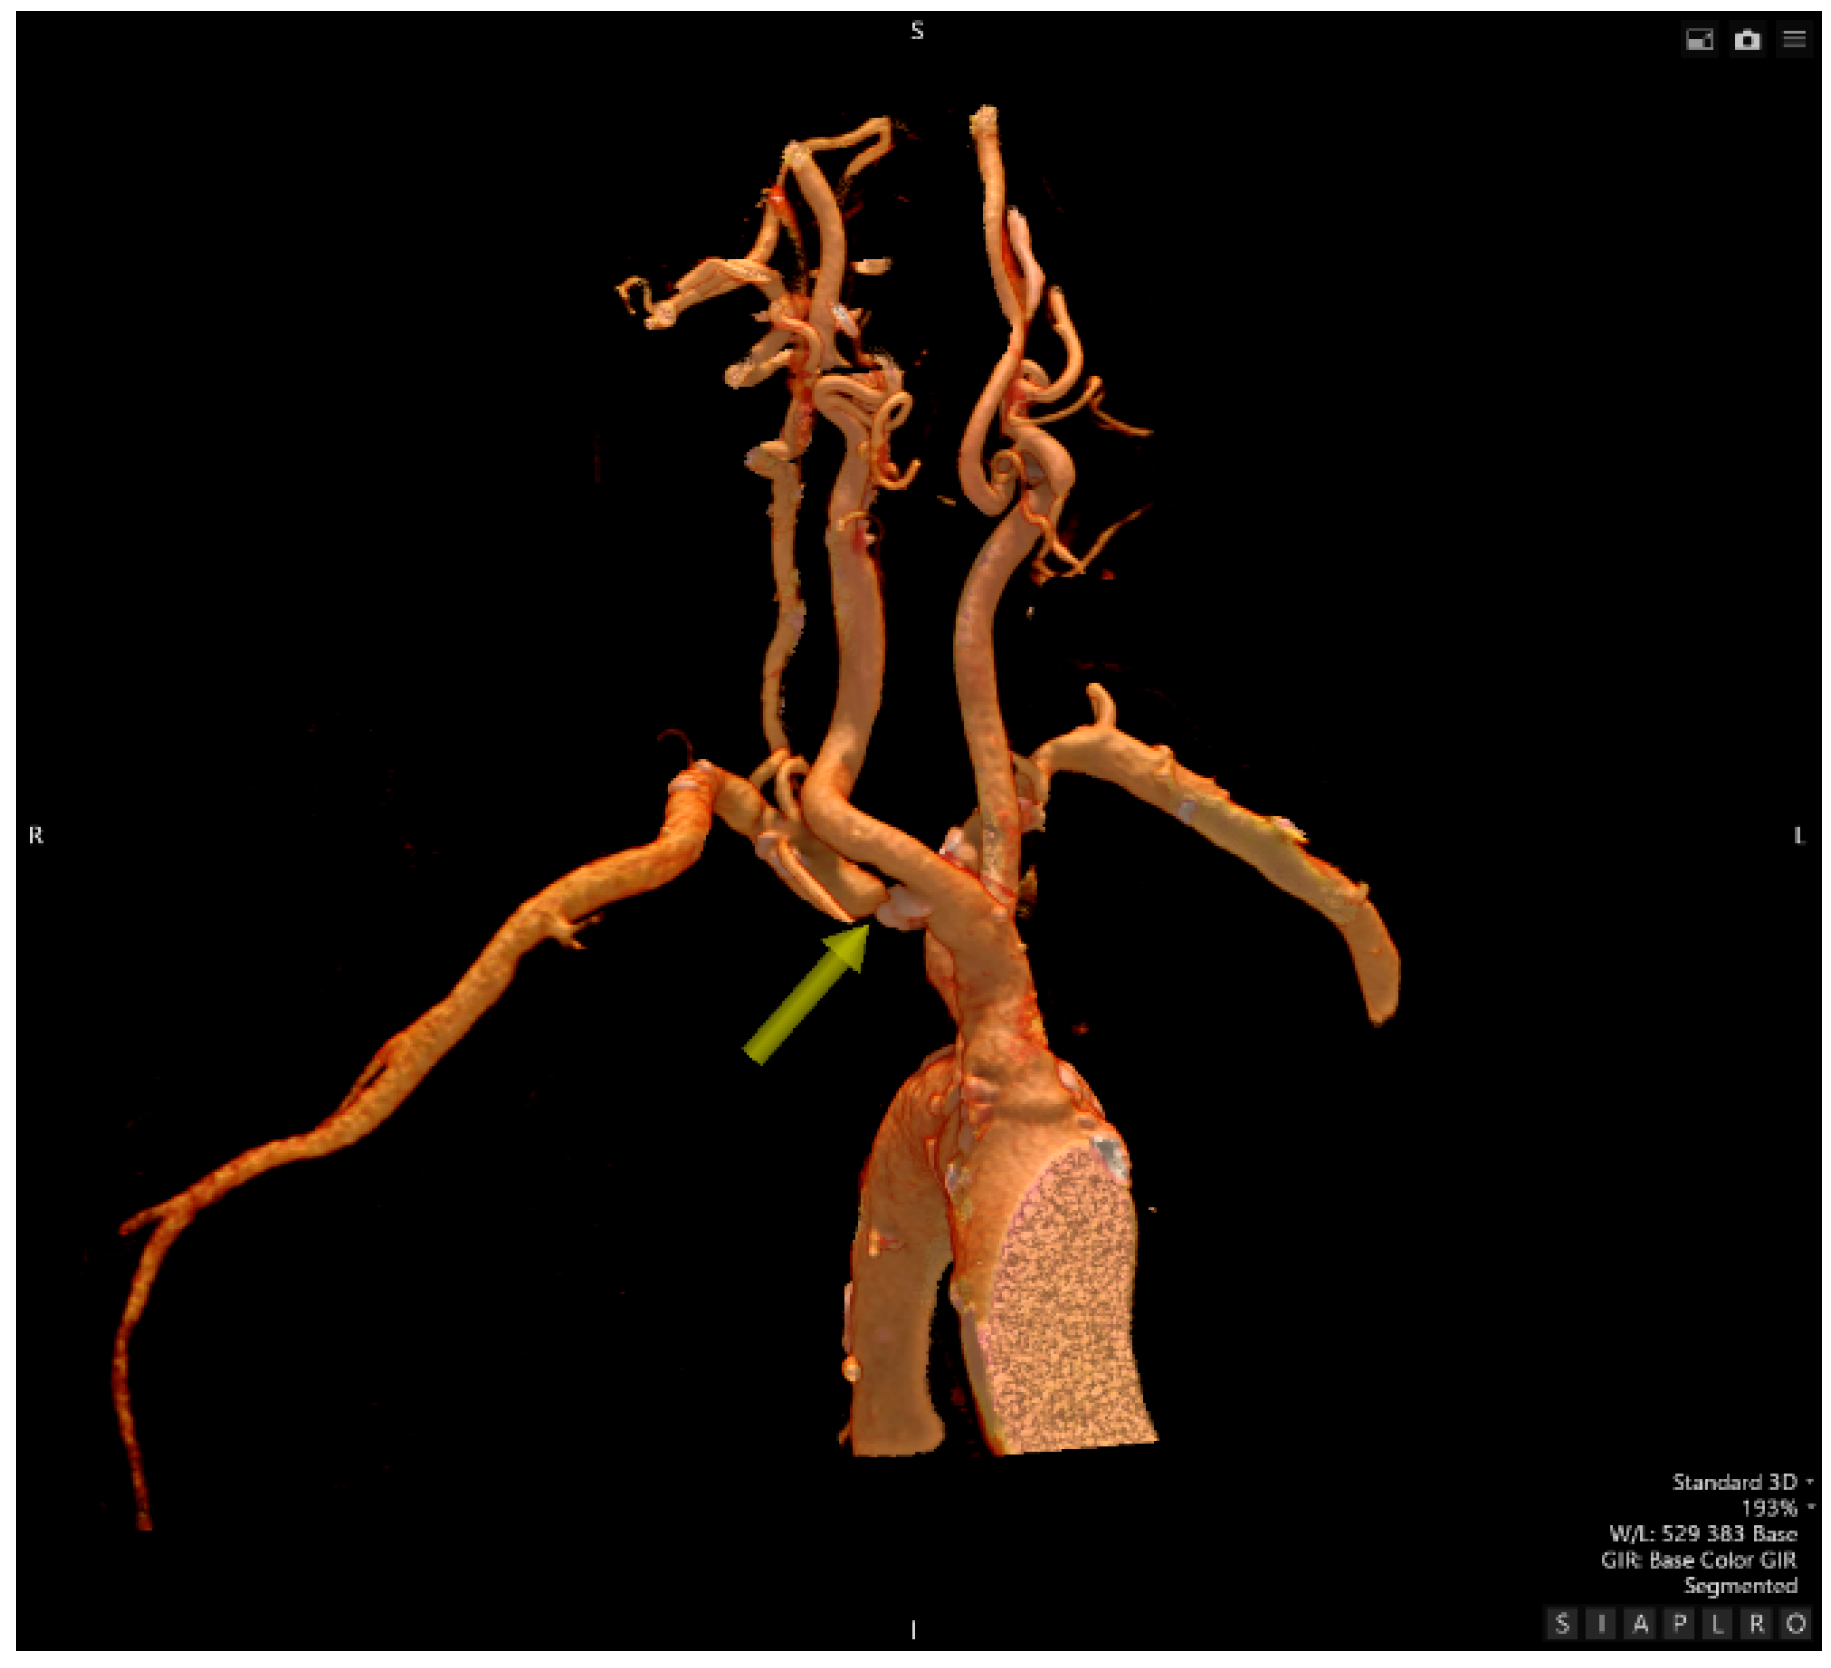

- Computed Tomography Angiography

- Interventional Radiology – an attempt at recanalization of the right subclavian artery